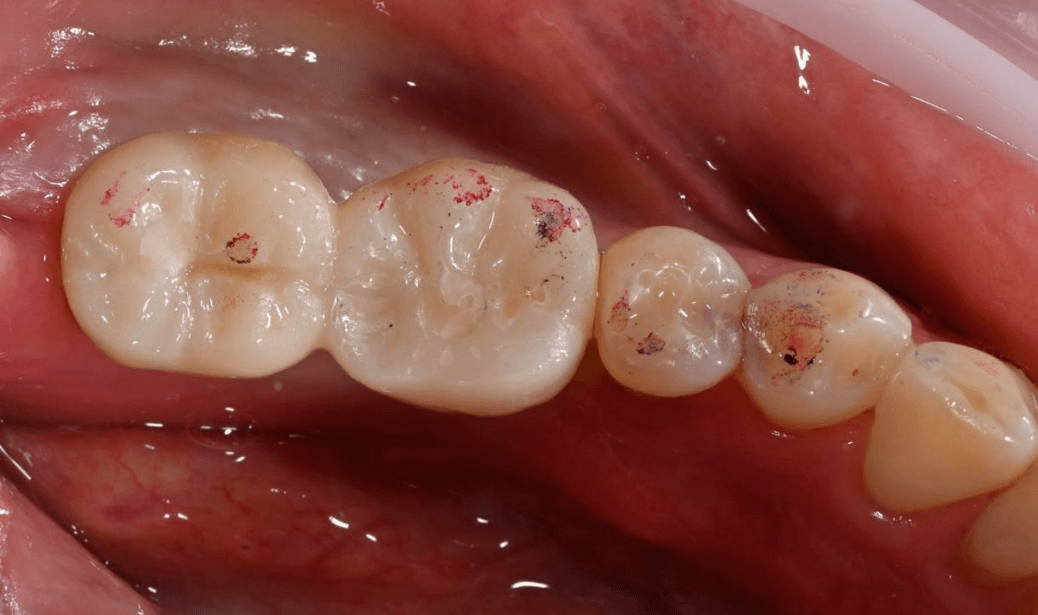

Прекрасный результат через 3 месяца и постоянное протезирование сразу без временных реставраций.